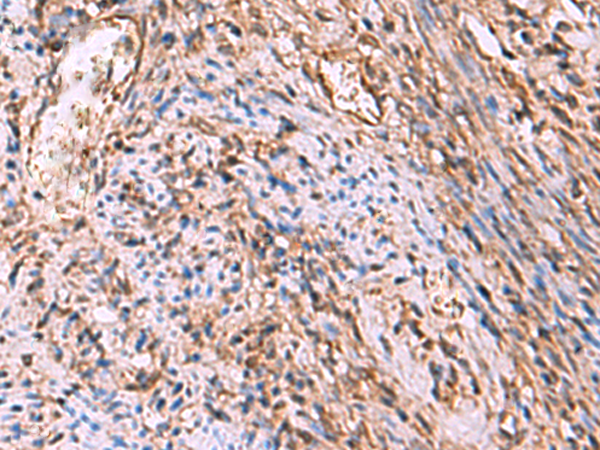

分类: 科研抗体货号: P10169别名: HMDRA1; FLB7527; PRO1999应用: WB,IHC反应种属: Human, Mouse, Rat